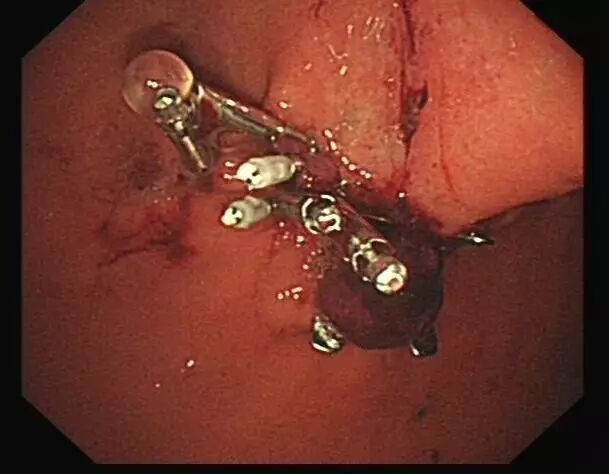

OTSC在消化道出血治疗中的应用

内镜夹怎么不掉CJP每周一帖--OTSC吻合夹系统在经内镜治疗消化道出血、穿孔及瘘中的应用_https://www.jmylbn.com_新闻资讯_第10张